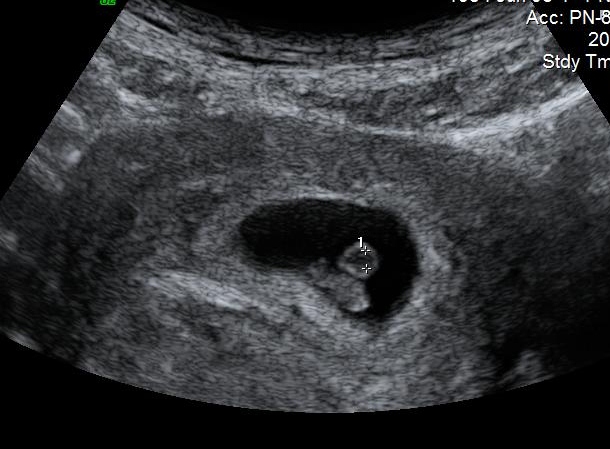

Hi everyone. This is my abdominal ultrasound at 7 weeks. Can anyone tell girl or boy?? Attachment 8685